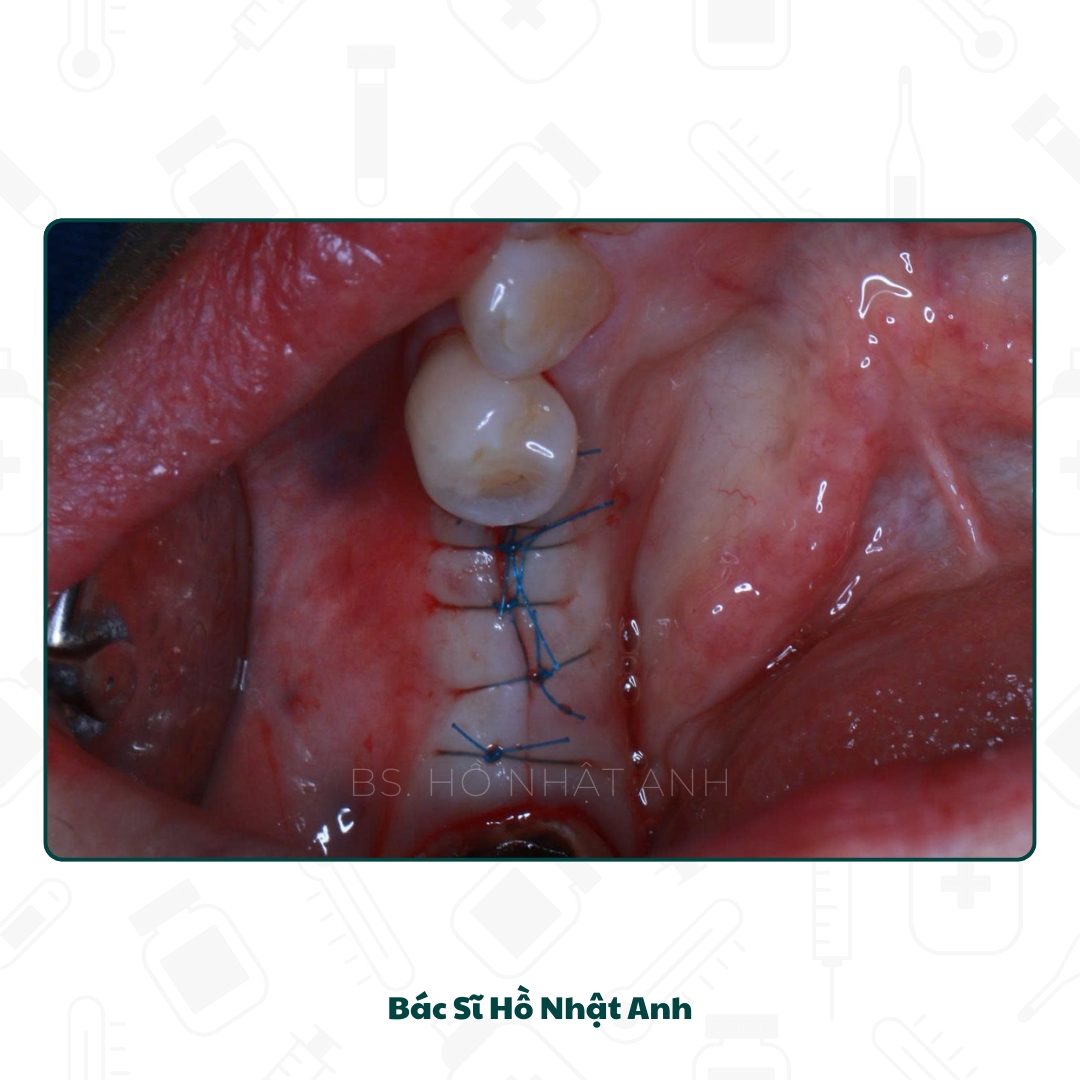

Quy trình cắm Implant, Ghép xương, xử lý mô mềm Và Lắp răng

Quy Trình Cắm Ghép Implant